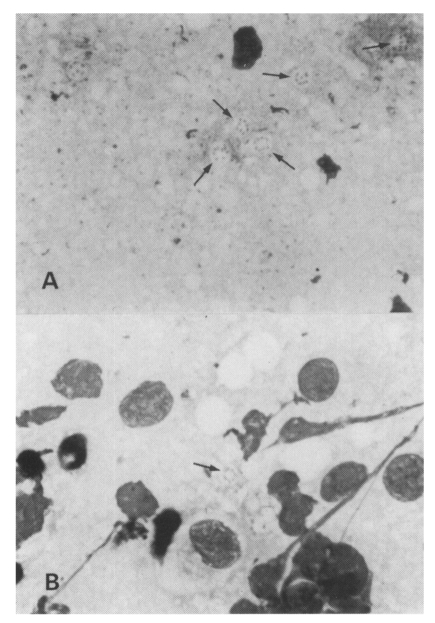

Is Pneumocystis carinii vertically transmitted to neonatal rats?

The Korean Journal of Parasitology 1999;37(3):149-156.